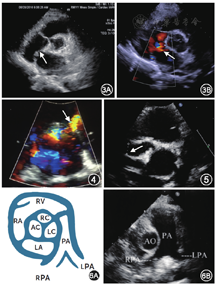

(6)观察房间隔的完整性,有无房间隔缺损、膨出瘤等。例3:房间隔缺损(图3,视频5)。

注:RV右心室;RA右心房;LA左心房;RC右冠瓣;LC左冠瓣;AC无冠瓣;PA主肺动脉;AO主动脉;RPA右肺动脉;LPA左肺动脉

(7)室间隔缺损的分型。例4:室间隔缺损(图4,视频6)。

(9)观察左、右冠状动脉开口及主干有无病变(冠状动脉开口异常、扩大、狭窄或闭塞)。例5:川崎病患者的右冠状动脉扩张(图5)。